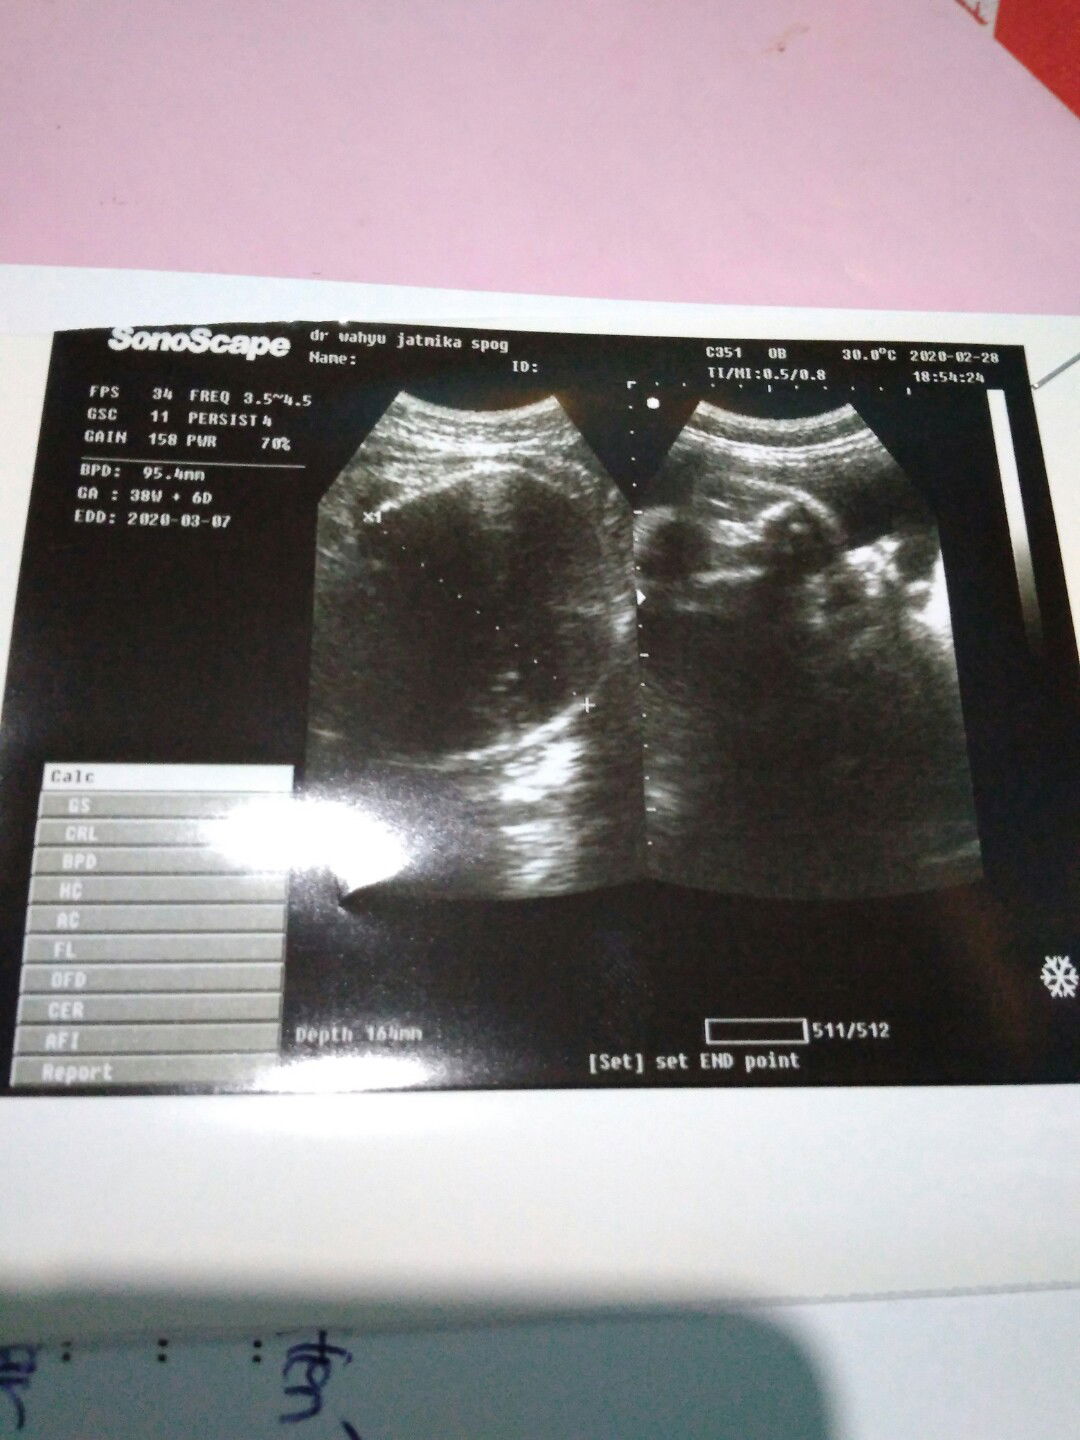

lupa tanggal haid terakhir

Bunda minta solusinya dong yang pernah mengalami lupa tgl trkhir mens bund, saya bingung dengan hasil prediksi bidan sama hasil USG dokter hpl nya beda 5hri bunda kalo bidan saya hpl nya 2maret kalo di usg dokter hpl nya tgl 7maret bunda, saya harus percaya mana yah bunda, soalnya saya juga lupa tgl trkhir mens saya cuma memang beda 5hr saja, menurut bunda lebih percaya sama perkiraan bidan apa sama hasil USG yah Bun?? Karena hpl yg dari bidan sudah lewat 5hr tetapi kondisi janin dan ketuban masih sehat dan baik* saja bunda kalau kontrol pasti bilangnya bayinya sehat* terus, tolong pendapatnya bun.